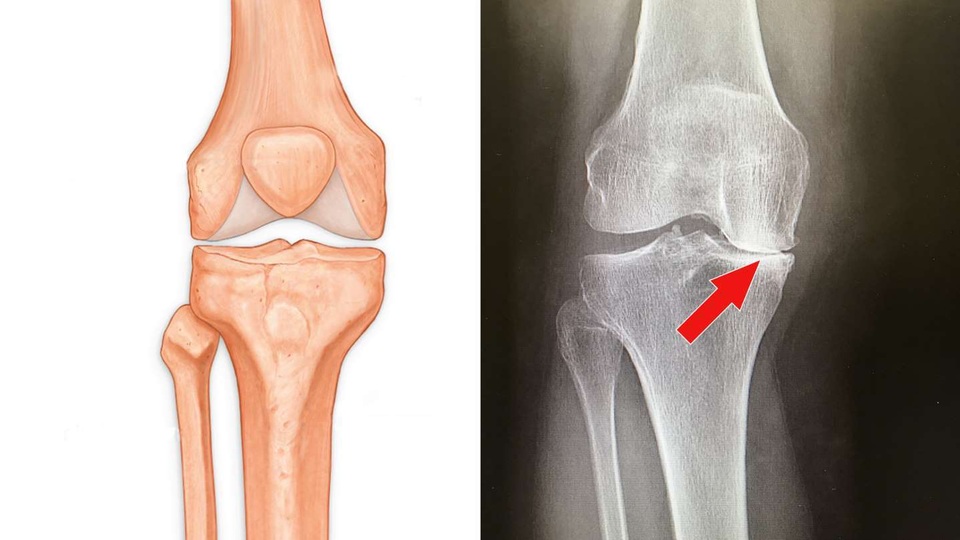

3. Thoái hóa khớp gối

Thoái hóa khớp là loại viêm khớp phổ biến nhất, đây là tình trạng hao mòn của lớp lót bề mặt khớp, là nguyên nhân phổ biến nhất gây đau khớp gối ở những người trên 50 tuổi và có thể hạn chế hoạt động của họ. Điểm chính cần nhấn mạnh ở đây là chúng ta không muốn khớp gối bị đau gây ra các vấn đề khác về sức khỏe. Ngồi yên một chỗ và cảm thấy hối tiếc cho bản thân là điều tệ nhất mà bạn có thể làm! Vận đông bên gối bị viêm, và tăng cường các cơ xung quanh đầu gối, có thể tạo ra một sự khác biệt rất lớn.